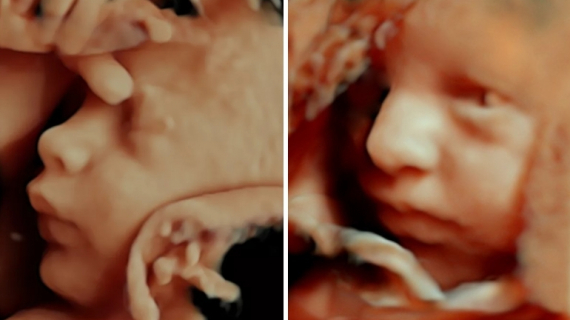

• Amazing Things Fetuses Do in the Womb

Pregnancy Videos

Amazing Things Fetuses Do in the Womb

• 40 Weeks Pregnant Ultrasound

• 40 Week Pregnancy Animation